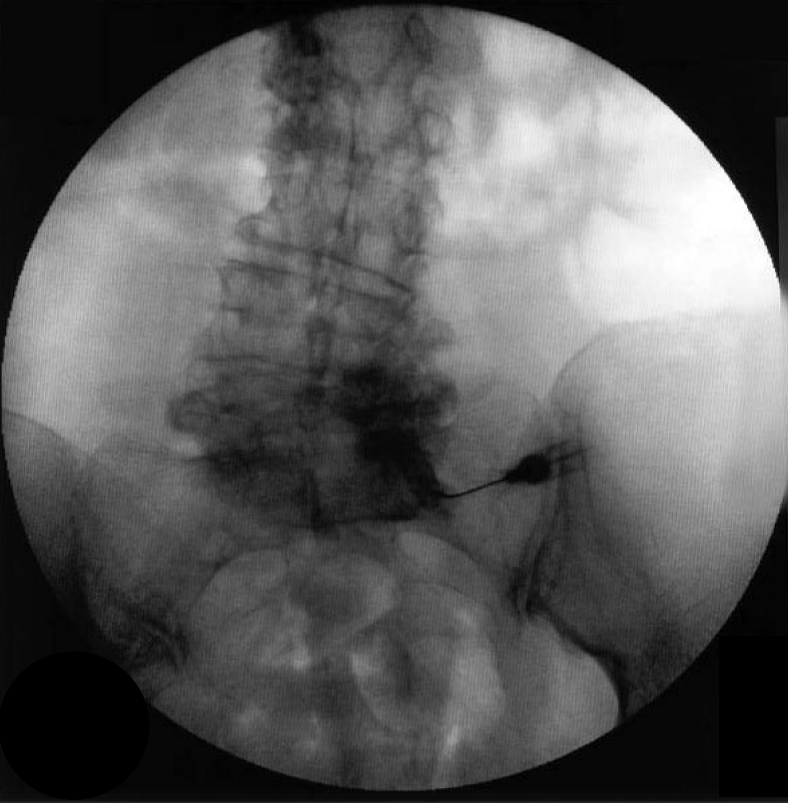

Case 3 (湘雅二医院)

- 王某某,女,63岁,反复腰痛10年

- 3个月前加重并出现右侧臀部疼痛,沿右侧大腿、小腿后侧及外侧放射,右侧为甚,伴间歇性跛行(50米)。

- 体查: L4/5及右髋部压叩痛,右下肢感觉减退,右髋关节活动明显受限,双侧直腿抬高及加强试验(-),右侧4字征(+),右侧托马斯征(+)

- 诊断:L4/5滑脱症合并右侧髋关节OA

- 治疗:先行脊柱减压融合,2年后行右侧THA,随访疗效满意。